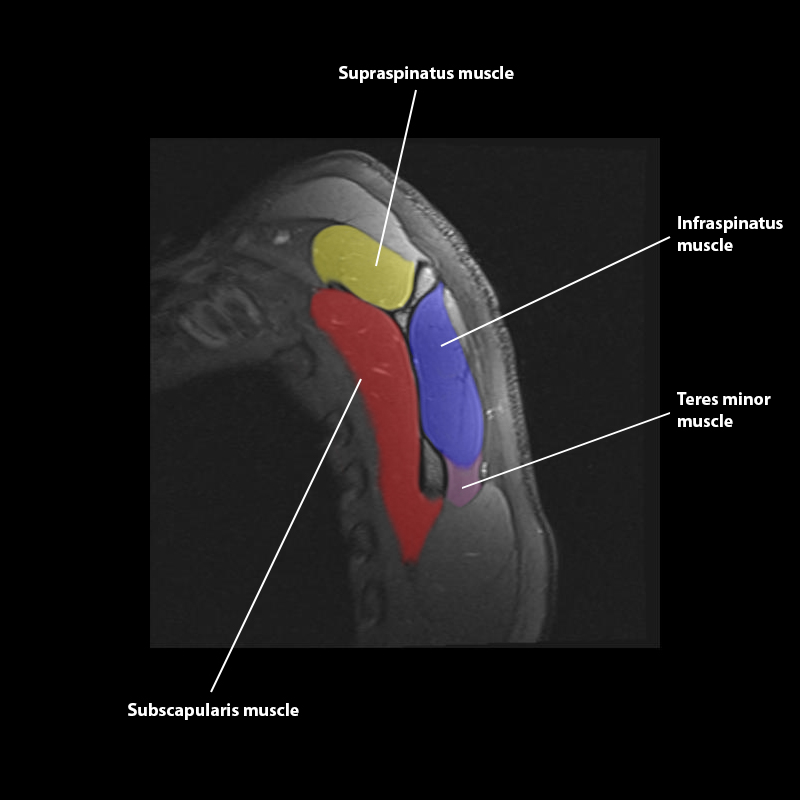

Shoulder MRI Anatomy